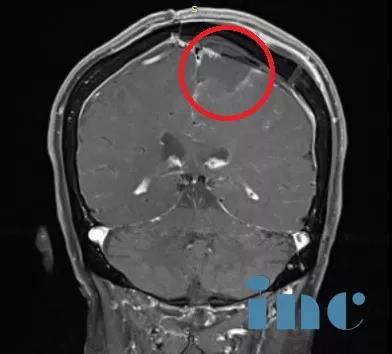

手術(shù)過程:左側(cè)額葉到額頂葉旁矢狀面的成骨性環(huán)鋸術(shù)和顯微外科腦膜瘤切除術(shù);自體骨膜移植的硬腦膜成形術(shù)。

術(shù)后影像資料:腫瘤肉眼下全切,可見局部組織缺陷,水腫效應(yīng)存在,被壓迫正常腦組織緩慢復(fù)位。